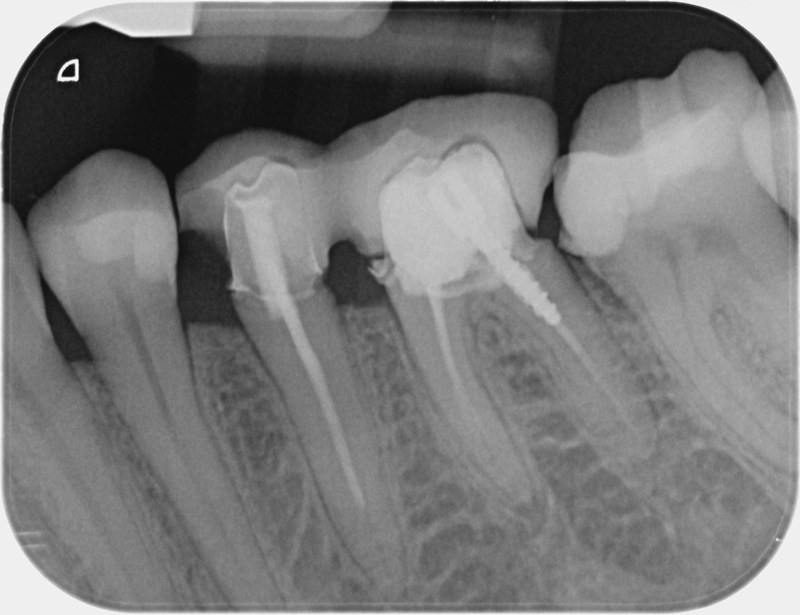

• Traitement endodontique : Sous anesthésie locale et à travers la protection d’un champ opératoire nous accédons à la pulpe de la dent à soigner, puis aux canaux de ses racines que nous devons désinfecter. Ce soin nécessite l’élimination complète de la source de contamination (souvent la carie) parfois sous une ancienne reconstitution ou une couronne qu’il faut alors retirer. Une fois le nettoyage et la mise en forme des canaux réalisés, nous les obturons de façon hermétique avec un ciment et un matériau thermoplastique appelé Gutta Percha. Ceci afin d’empêcher une nouvelle prolifération bactérienne et d’assurer le maintien de la dent dans ses structures de soutien (ligament parodontal et os alvéolaire). L’ouverture effectuée au centre de la dent sera d’abord refermée avec un pansement provisoire avant d’envisager ensemble la reconstitution d’usage : un composite, un inlay-onlay ou une couronne.

Avant

Après